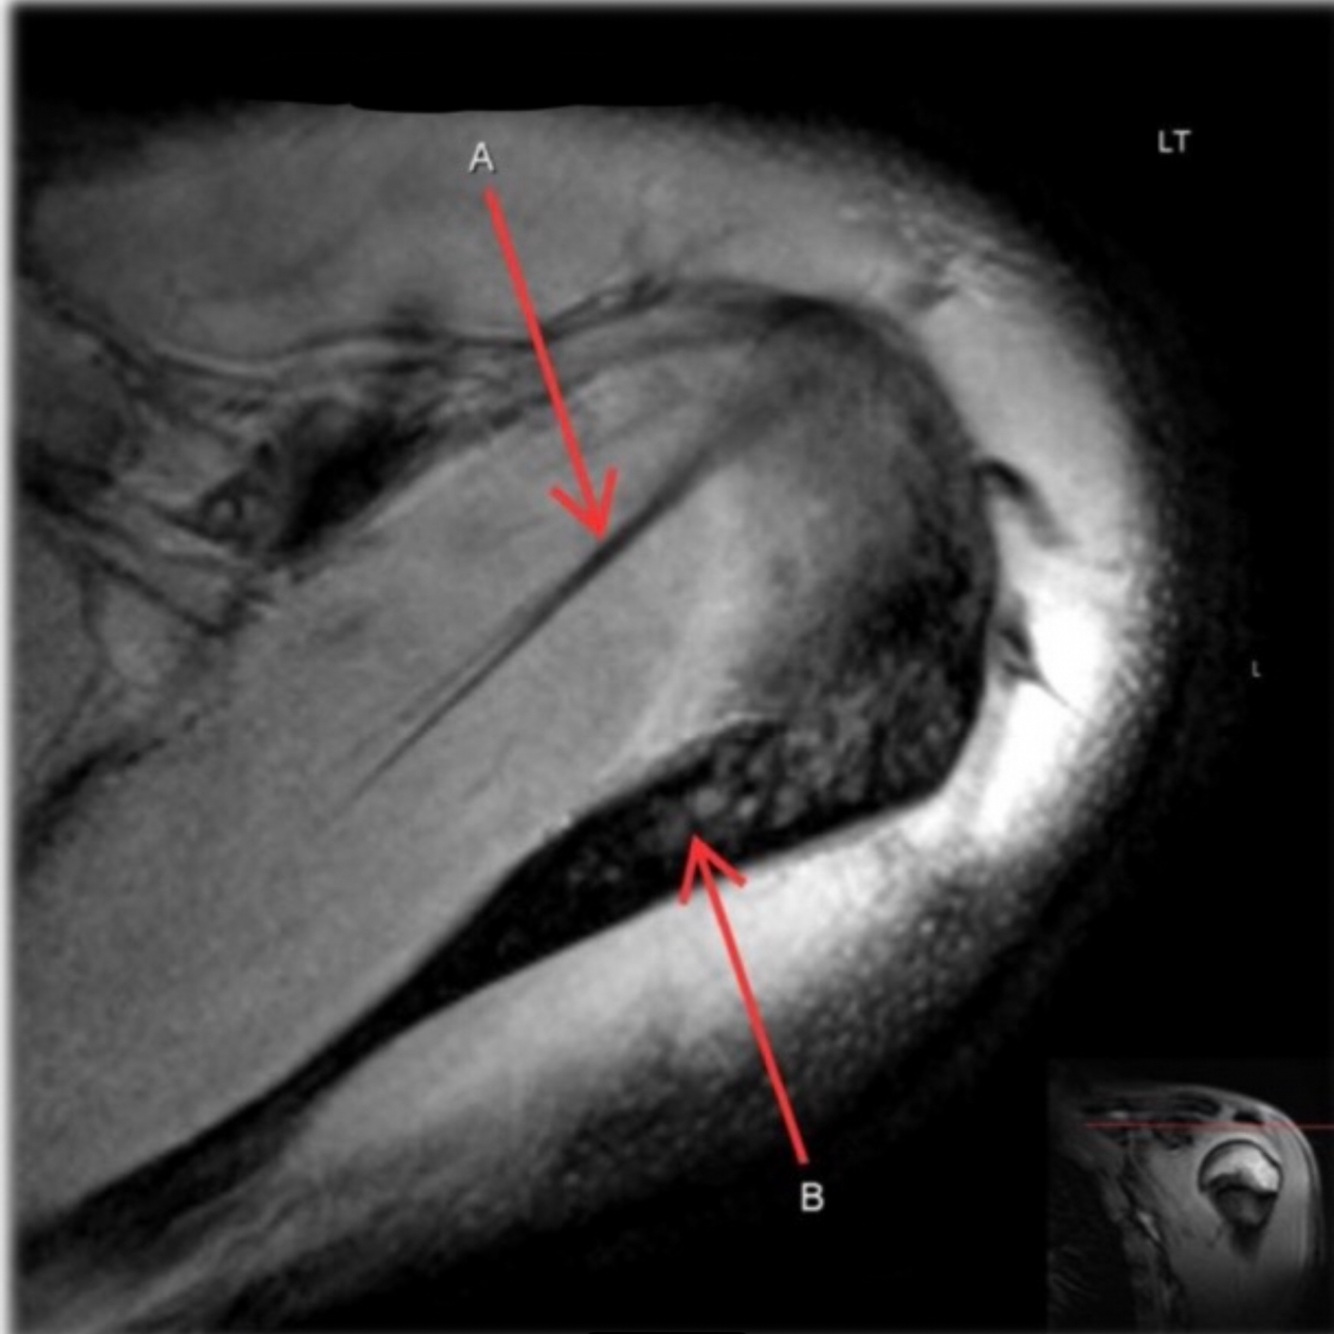

What is letter A?

ACHILLES TENDON

144

What is letter B?

CALCANEUS

145

What is letter C?

TALUS

146

What is letter D?

TIBIA

147